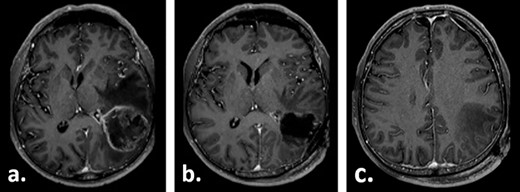

Fifteen weeks after tumour resection and 4 weeks after hygroma evacuation, the patient presented again with concentration loss, fatigue and a moderate right-sided hemiparesis. A new CT scan revealed a strongly progressive subdural hygroma with a 3-mm-thick subdural membrane. The hygroma was evacuated through the same burr hole; however, due to an unsatisfying hygroma regression, a subduro–peritoneal shunt for permanent hygroma drainage was implanted subsequently. During these both procedures, a thick greyish subdural membrane was noticed, but no tissue samples were taken. Despite the volume reduction of the hygroma, its membrane still caused a considerable mass effect. Few days after the last surgical procedure, a cerebral MRI was performed following the tumour follow-up protocol. On this imaging, the subdural membrane over the left hemisphere presented as an inhomogeneous contrast-enhancing lesion with irregular contours (Fig. 3).

Gadolinium-enhanced T1-weighted axial MRI of the patient 16 weeks after tumour resection demonstrating the resection cavity (a) and progressive subdural fluid collection with the newly occurred contrast-enhancing membrane (b).